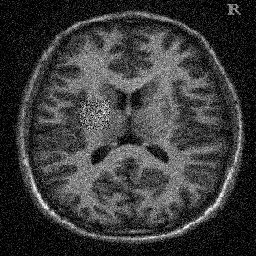

4.1. Uniform Gaussian noise

In this first experiment, we consider the denoising problem with brain scan images. The first set consists of images of pixels and Gaussian noise with zero mean and variance . The original and noisy images are shown in Figure 4.1. The domain decomposition-semismooth Newton algorithms run with the parameter values , , and . The results are shown in Figure 4.2. From the surface representation of , we can observe that is continuous and its shape is related to the one of the original image. In particular, the regularization is stronger in homogeneous regions in the image, and weaker where the image intensity undergoes variations on a smaller scale.

In Table 4.1 the performance of the different methods is compared. For all of them, only the first 2 domain decomposition iterations were considered. The total number of SSN iterations differ at most by one. The impact of the domain decomposition method becomes clear when comparing the computing times of the methods, corresponding to one, two and four subdomains. The computing time is significantly reduced. The effect of the optimized transmission conditions can be realized when comparing the gap between subdomains, which is much lower in the case of optimized transmission conditions () than in the standard Schwarz method ().